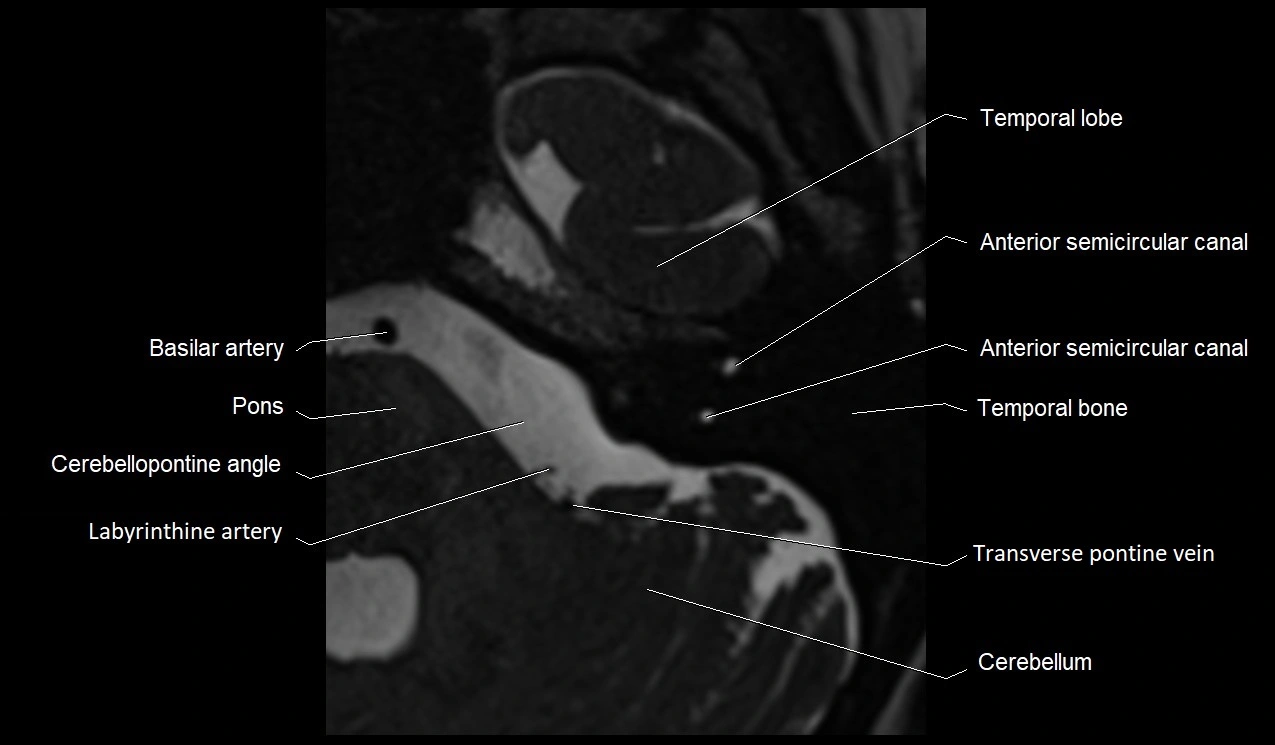

MRI images

image